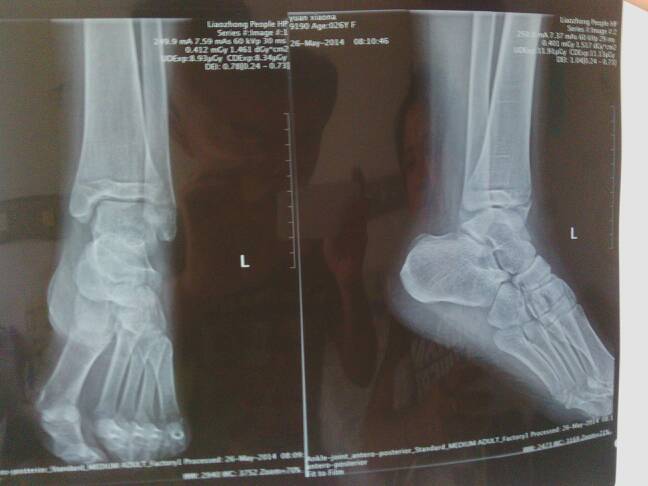

敬请老专家解疑。 左内踝骨折,石膏外固定,4日初诊与14日复查时拍的片子一样位置很好。一个月经大夫允许开始拄拐下地轻微锻炼。  次月13日(已39天)复查拍片显示内踝侧面长的挺好,前踝向下移位约2~3毫米,主治医师说没事,又挺了十多天(次月26日)拍片还是一样依旧错位。   医生有的说没事,有的说应该手术弄不好还要移骨,(怕留后遗症)唉,搞得我头都大了!请经验丰富的老教授、专家帮帮我吧!

这个手术一般是不需要做的,但是活动锻炼的幅度和力量需要适当减少了,不能让移位再加大了。从照片上看,这个踝关节的骨骺线都是存在的,说明还是年轻人,而这个前踝是有骨折块的移位的,这个是属于关节处的骨折,骨折移位影响到了踝关节面的平整,一般来说关节面处的骨折,以恢复解剖复位为好。但是这个地方因为骨骺还没有...闭合,做手术不好固定,就是螺钉固定,也容易损伤骨骺,而影响到发育,所以一般是保守治疗,减少活动的幅度和力量,这个移位,以后一般是可以自行渐渐生长好的。